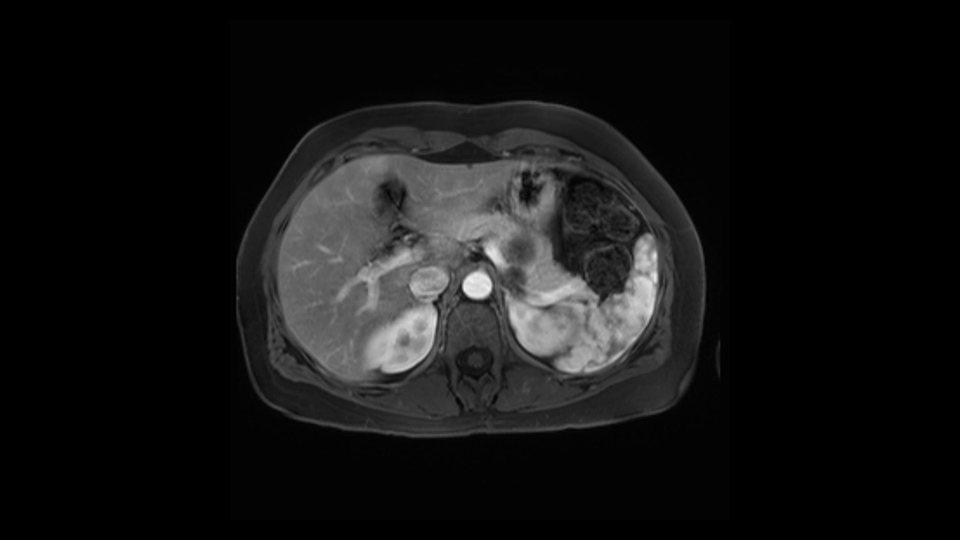

The lesion itself is quite adjacent to and abuts the splenic vein and therefore we need to anticipate that these two structures will be intimately related and possibly impossible to separate between the two.

The lesion also is quite posterior. While the plane between the cyst and the left adrenal gland is often preserved, we do have to pay attention here so that we remain in the right plane and maintain our margin here. Occasionally in these cases, en bloc adrenalectomy needs to be performed.

In terms of maintenance of the regular planes, other factors that we need to consider is whether you need to enter in posteriorly to Gerota’s fascia to obtain an adequate margin and anteriorly to ensure the tumor can be mobilized safely off of the posterior wall of the stomach.

In light of these findings, on the cross sectional imaging which include MRI, our plan would be to perform a laparoscopic distal pancreatectomy. I think based on oncologic grounds, a spleen preserving procedure is probably reasonable. From looking at the scan, its likely technically possible although a vessel preserving procedure is likely not appropriate for this patient. Technical intraoperative factors will certainly influence that decision.

The second slowing down moment or consideration I give to a distal pancreatectomy is the anatomy of the portal vein and the splenic artery. And so I look here and the anatomy is pretty straightforward. The splenic vein comes off normally and runs behind the pancreas and I can see the artery superior to that, again coming off in a normal manner from the celiac axis. So those two things, the portal vein and the splenic artery will be taken normally in this procedure.

The third consideration in a distal pancreatectomy is whether I take the spleen or preserve it and I will try to always preserve it if I can. If it can be done safely and without too much difficulty or risk of bleeding. So the couple of considerations on the imaging that I look at is: Is the tail of the pancreas firmly embedded in the hilum of the spleen? I can see here that it isn’t and that it would likely be possible to preserve the spleen and I also look at the vessels and see whether the vessels are kind of firmly kind of intertwined in the distal part of the tail or whether we think we can actually separately take them with a stapler and remove all the tip of the tail of the spleen. So I think this would be a good candidate for a Warshaw technique, which is not preserving the splenic vein or artery but rather taking them as a segment and preserving the spleen. After this, the spleen would be getting all the blood supply from the short gastrics of the stomach. So that’s the third consideration in a distal pancreatectomy and the final thing is the retroperitoneum.

The preoperative MR is very very important; any scan for that matter. Whether it is a pancreatic protocol CT scan or the MR as presented, the diagnostic imaging plays a very big role. And with this we see that it’s a very well-defined cystic focus in the body of the pancreas. Although there are septal enhancements, very well demarcated, but there is no vascular involvement. However, the mass appears to be in contact with the splenic vessel, and the mass is also a little bit in touch with the left adrenal and also the loop of bowel. So looking at this, basing on the features, I think it’s probably a mucinous cystic lesion, it could possibly be a pseudocyst. But basing on the history, it appears like there is no history that would point out to a pseudocyst. And not an IPMN as well; I don’t see any side branches from the MRCP and the MR scan and although there is no axial T2 images available, and I truly find it easier to identify the septations on T2, and the hepatic cyst that is visible on this scan makes it hard to differentiate it from a simple or complex cyst which may be considered in a mucinous neoplasm with cystic or mucinous metastasis. Basically the contrast would help us in identifying the enhancing mural nodules or septations in the cysts. The MRCP is definitely helpful to identify if there is any side branch, if we are considering any IPMN.

Key features that I look at the imaging are: first I look at the distance between the cyst and the portal vein SMV confluence. So there are guidelines for this, they call the Yonsei guidelines, to decide to do it laparoscopically or open and basically it says that if it’s a cancer, at least a centimeter away from the celiac trunk or the venous confluence. This is a cyst. So maybe you could stretch that a bit, but you don't want to get into trouble there. So for this cyst if you look at it, it's nicely away from the confluence.

So unfortunately I cannot show you a coronal view but you can see it easily on this scan, going down first you see the celiac trunk and you see here, quite a nice distance between the celiac trunk and the beginning of the mucinous cyst. And if you go up here and follow down the portal vein confluence you also see a nice distance there.

So what I would normally do in these patients, I would look at the abutment of any other organs, one, which is here, potentially the adrenal gland and two the small bowel. And two, look at the distance from the vessels which I would normally do in a coronal view. So you can easily measure the distance and third I look at the insertion of the inferior mesenteric vein. Now we can probably also see that on here. Although it's better on a CT scan and it's better on a coronal view, you want to know where the inferior mesenteric vein comes into either the splenic or the SMV, because that is typically a very important slow down moment when you mobilize the lower portion of the pancreas knowing where the inferior mesenteric vein comes in either the splenic vein or the SMV. So those are I think the three most important points for the CT scan.